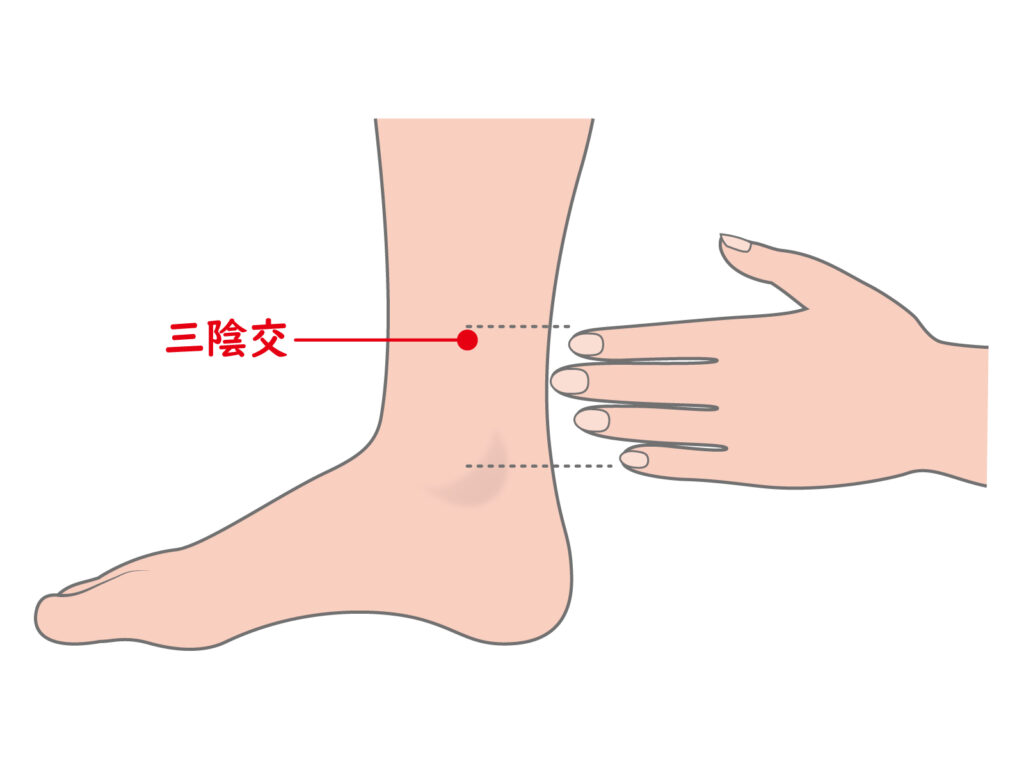

痔に対する鍼灸 – 横浜市旭区の鍼灸・整体なら うさぎ鍼灸整体院 肩こり・腰痛・不妊未妊・逆子鍼灸 希望ヶ丘駅徒歩8分。

痔の鍼灸 ~痔に効くツボとは~加納渡辺病院 岐阜市 乳腺外来・痔核手術・内視鏡・漢方外来。

痔を解決するツボはこれだ!鍼灸師が絶賛おかだ鍼灸院。

痔を解決するツボはこれだ!鍼灸師が絶賛おかだ鍼灸院。

痔東京・渋谷・恵比寿で鍼灸を専門に行う赤岩治療院。

痔に効くツボと漢方 東洋医学の観点から解説- 小顔矯正・整体を東京でお探しならRevision。

痔の鍼灸 ~痔に効くツボとは~加納渡辺病院 岐阜市 乳腺外来・痔核手術・内視鏡・漢方外来。

痔の鍼灸 ~痔に効くツボとは~加納渡辺病院 岐阜市 乳腺外来・痔核手術・内視鏡・漢方外来。

痔を解決するツボはこれだ!鍼灸師が絶賛おかだ鍼灸院。

痔に効くツボと漢方 東洋医学の観点から解説- 小顔矯正・整体を東京でお探しならRevision。

痔を解決するツボはこれだ!鍼灸師が絶賛おかだ鍼灸院。

悩む前にお試しを。痔にアプローチするツボ。健康クロワッサン オンライン。

痔に効くツボありますか?マッサージ・整体 杉沢はりきゅう院 健康美人。

痔に効くツボ 見つけ方と押し方を紹介 肛門周辺の血流を改善するツボと足裏ゾーン特選街web。